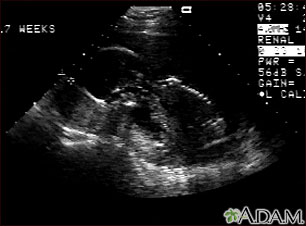

This is a normal fetal ultrasound performed at 17 weeks gestation. In the middle of the screen, the profile of the fetus is visible. The outline of the head can be seen in the left middle of the screen with the face down and the body in the fetal position extending to the lower right of the head. The outline of the spine can be seen on the right middle side of the screen.